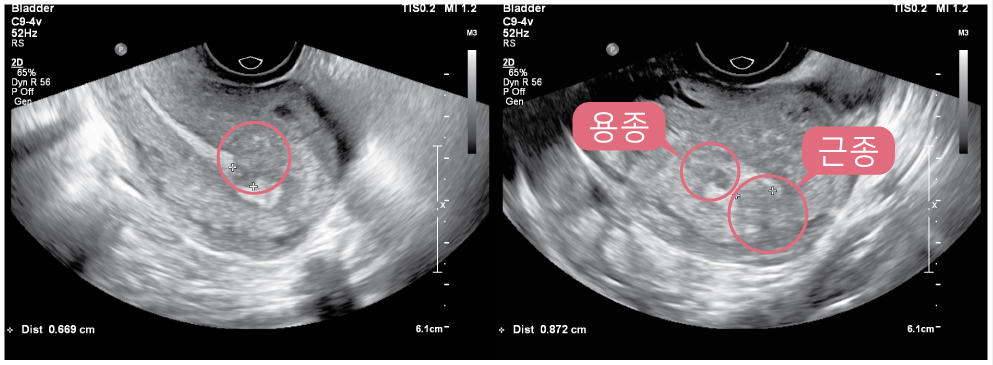

건강한 체중을 유지하고, 규칙적인 신체 활동을 하는 것은 자궁암뿐만 아니라 여러 가지 암의 위험을 줄일 수 있는 방법입니다. 또한, 고지방 식단을 피하고, 식물성 식품을 섭취하는 것이 좋습니다. 정기적인 산부인과 검진은 자궁암을 조기에 발견하는 데 매우 중요합니다. 특히, 자궁 내막증 변화를 조기에 감지할 수 있는 자궁내막 생검과 초음파 검사 등을 통해 건강을 관리할 수 있습니다.